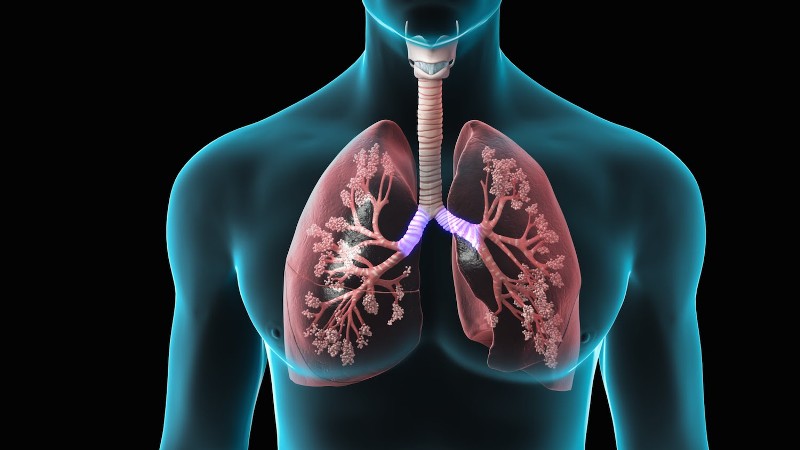

ANKTIVA: Η νέα ανοσοθεραπεία που ενεργοποιεί τα «κύτταρα-δολοφόνους» κατά του καρκίνου